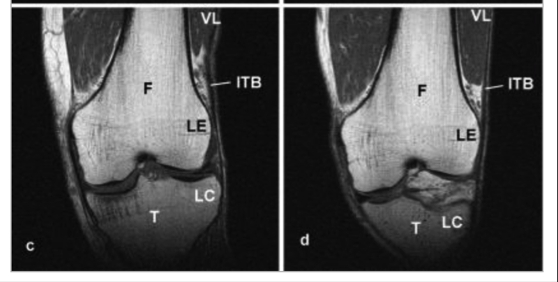

This is why other researchers postulate that this movement is merely an illusion as the ITB repeatedly tightens(6). With flexion, the patella moves along the femoral condyle and the tibia moves posteriorly. This tightens the ligamentous part of the ITB – ie the portion that attaches to Gerdy’s tubercle on the tibia and stretches the posterior fibres of the ITB tautly over the LFE (see figure 2). Evidence via magnetic resonance imaging (MRI) studies show that this tightening produces compression rather than friction in the area (see figure 3). Magnetic resonance imaging shows that compression against the LFE is greatest at 30 degrees of knee flexion(5).

In extension, the ITB slopes laterally away from the lateral epicondyle (LE) of the femur to the lateral condyle (LC) of the tibia. With flexion, the ITB is pulled medially toward the LC and closer to the LE, compressing the fatty tissue or synovial outcropping that lies underneath(4).